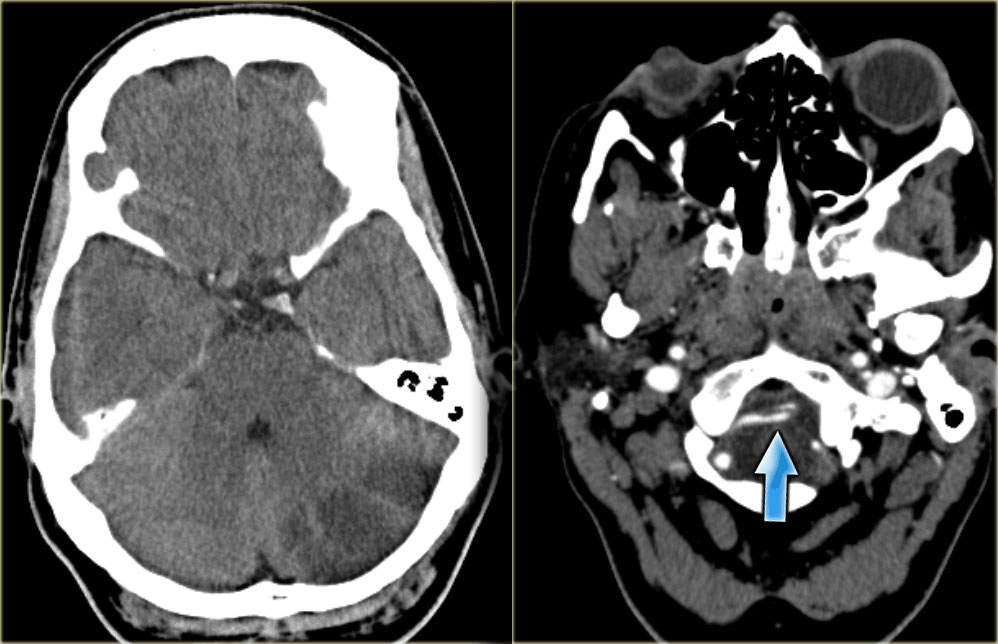

大脑后动脉梗塞(大脑后动脉供应丘脑、枕叶、中脑)

bd3aa55525aad65019d45b62f9cc5624.jpg

分水岭梗塞(外分水岭和内分水岭)

ce41b2b33f038df087e0d5b30c3599e4.jpg